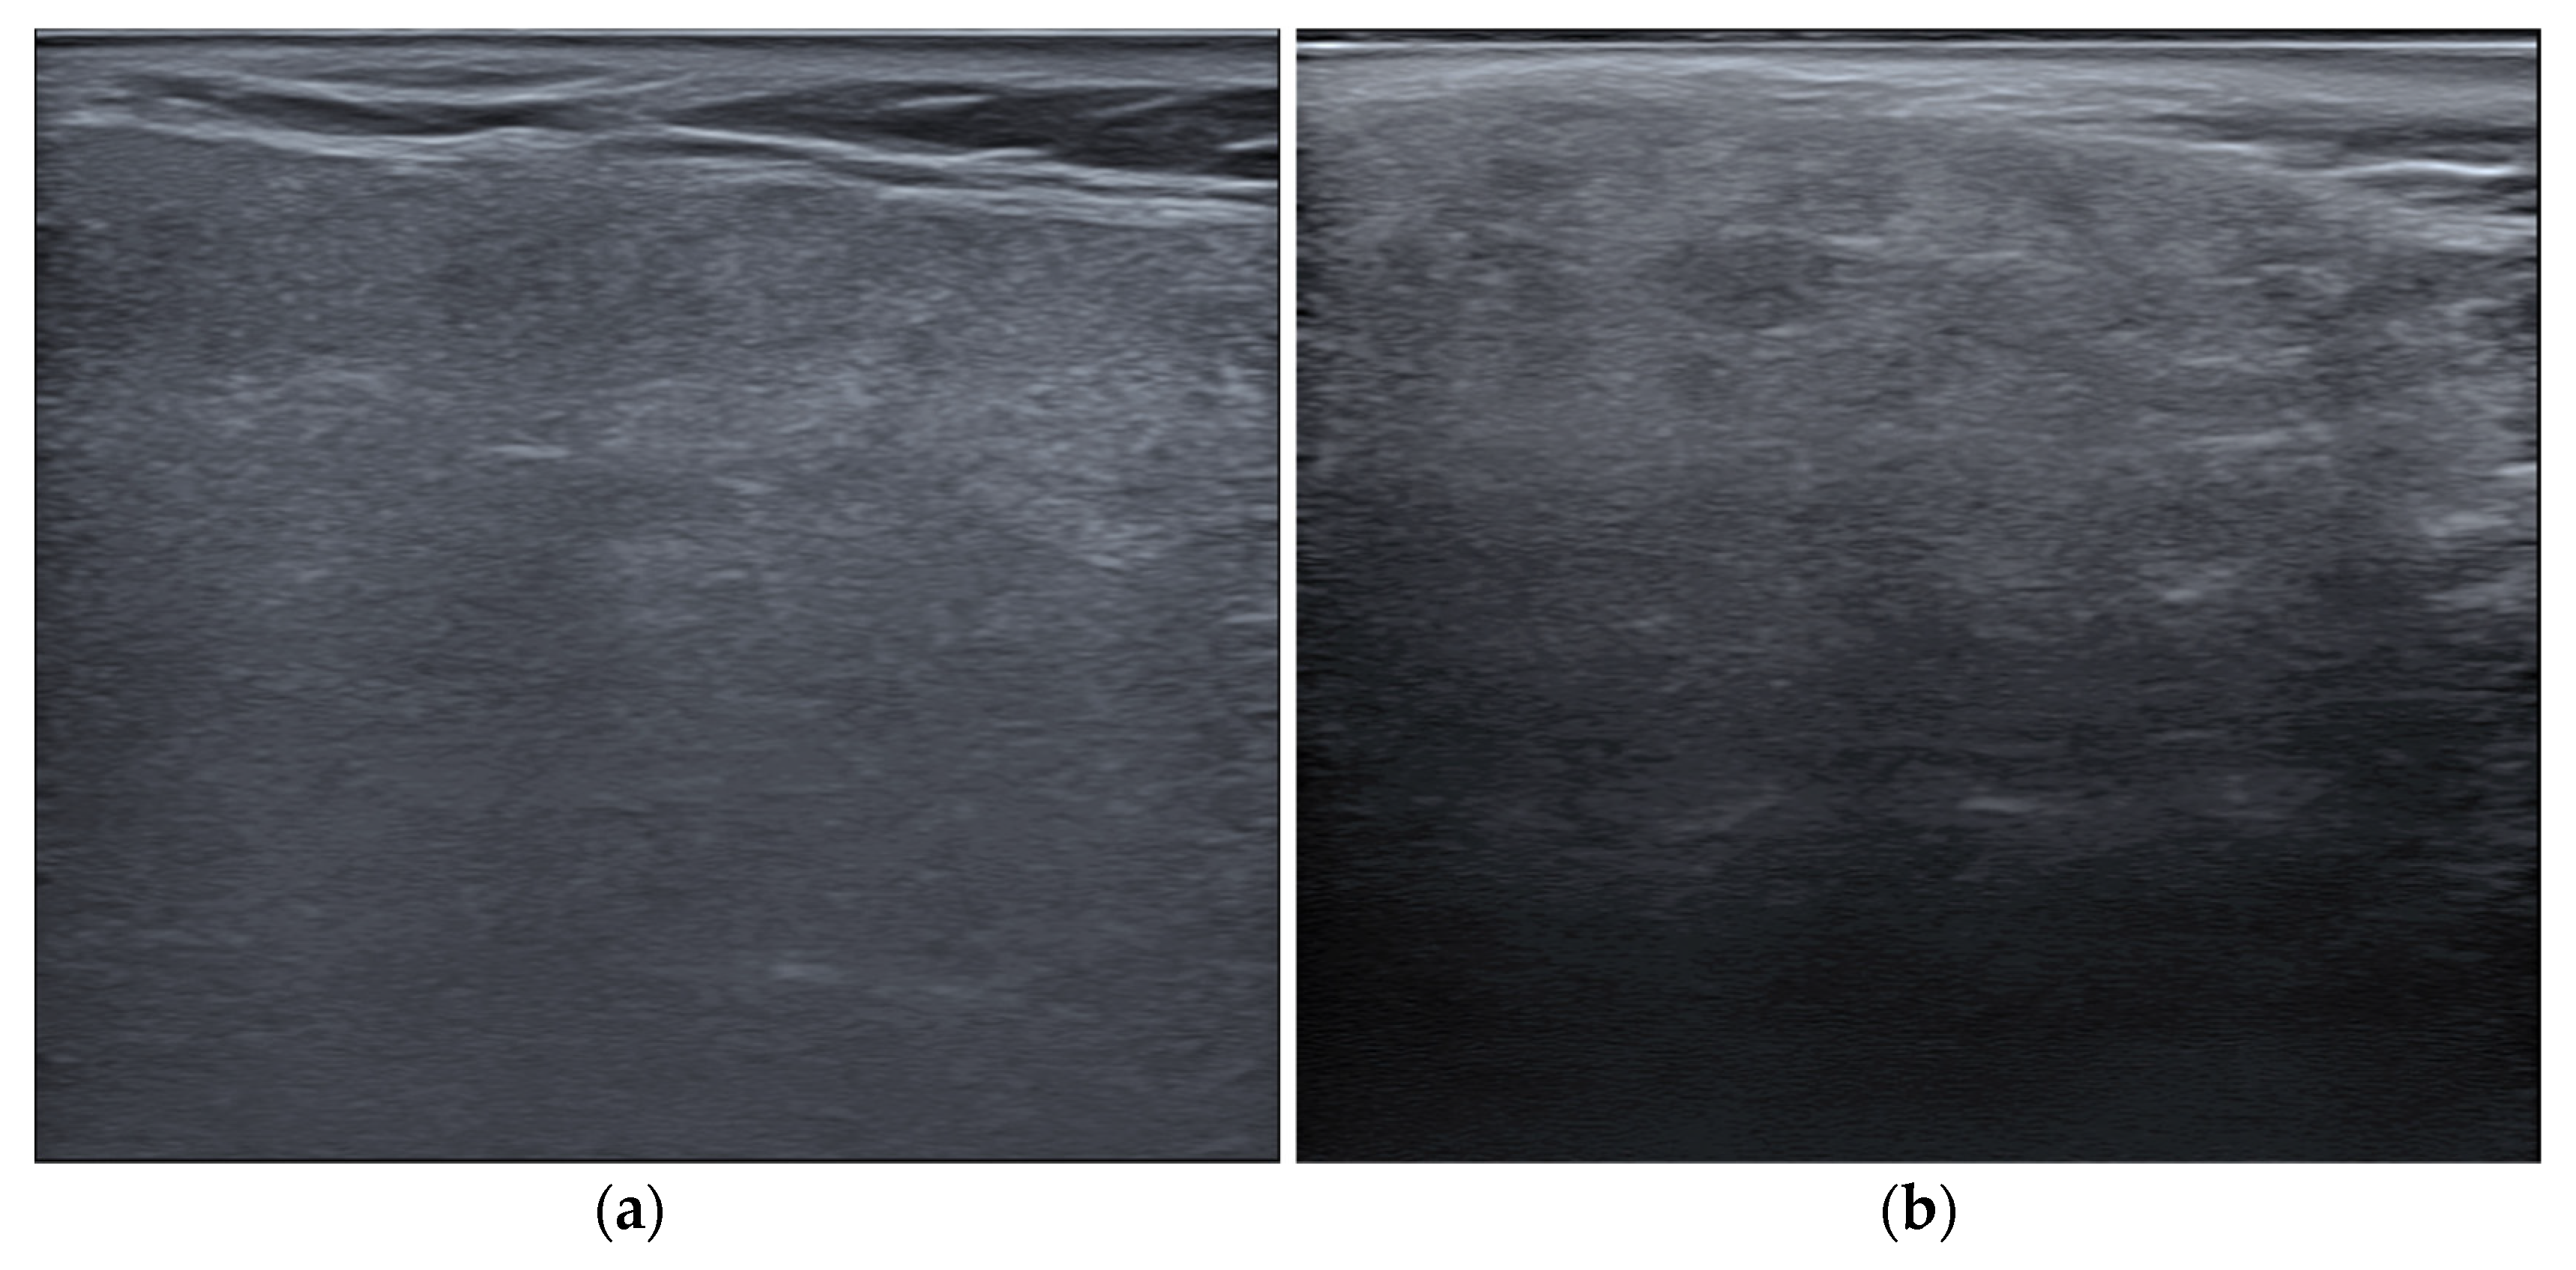

2.1. US Images